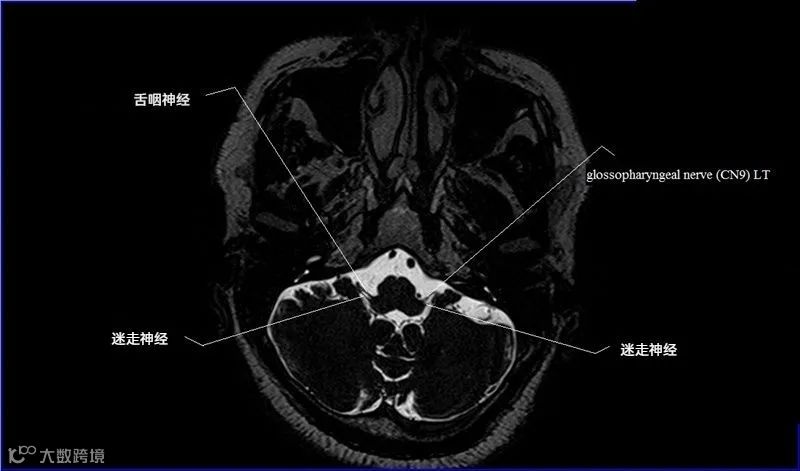

十二对脑神经口诀

一嗅二视三动眼,四滑五叉六外展,

七面八听九舌咽,迷走及副舌下全。